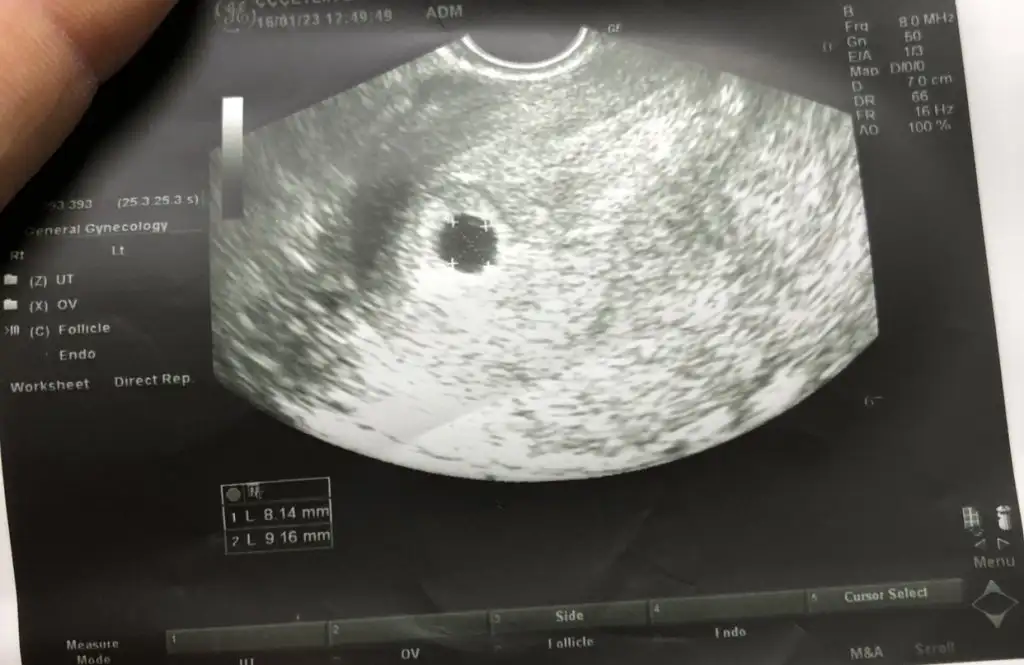

Merhaba kızlar pazartesi ultrasona girmiştim bebek görünmemişti dün lekelenme olunca tekrar gittim kese var ama kanama düşük tehlikesi olur dedi progestana devam dinlen ekledim ilk ultrasın ve 2 ultrasın keseleri bi bakrmısınıx kızlar kese içindeki beyazlar nedir acildeki doktor çok açıklama yapmadı sordum

• B0BA1324-BE4C-426A-AF5C-E8F58B831963.webp

B0BA1324-BE4C-426A-AF5C-E8F58B831963.webp

26,5 KB · Görüntüleme: 96

• 11715978-92FF-4AF6-92A1-3E5D96106CB1.webp

11715978-92FF-4AF6-92A1-3E5D96106CB1.webp

28,9 KB · Görüntüleme: 91

Ultrason prob hareketinden olan yansımalar onlar kaçıncı haftadasınız??